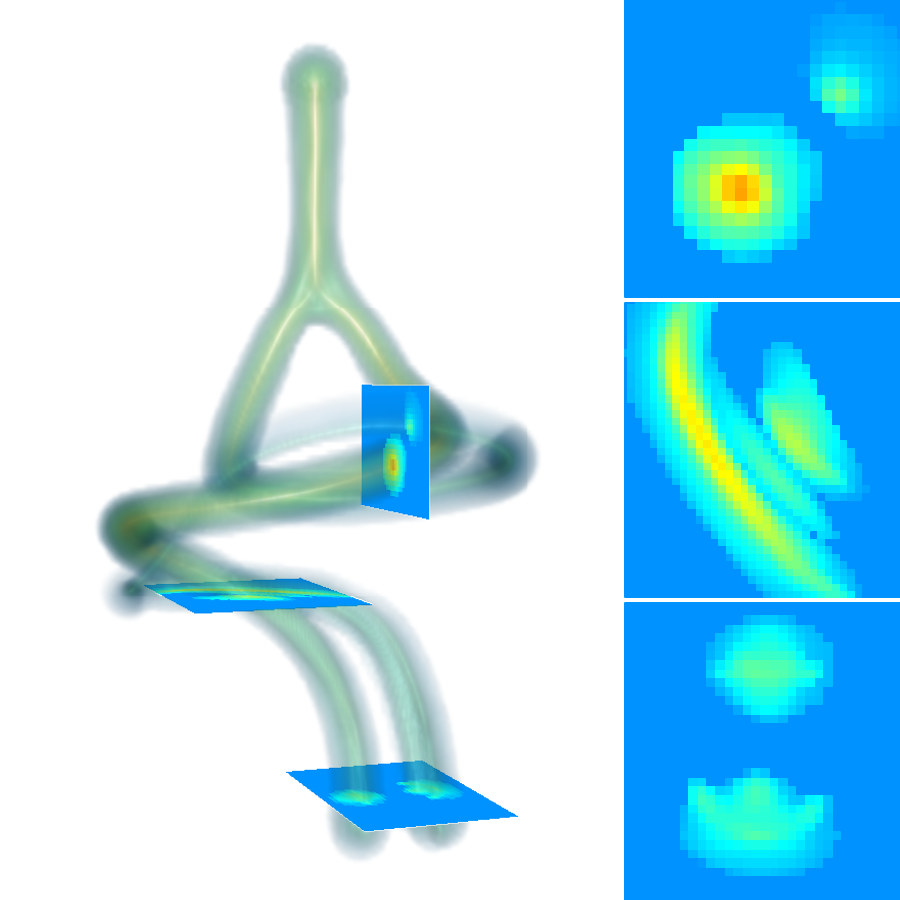

, , and modulate the respective components of the canonical Laplacian of Gaussian () filter oriented along the principal directions of . It is clear that given any arbitrary orientation as an orthonormal basis similar to , the proposed dictionary of filtering kernels can steer by computing the rotation transform, which maps the integral orientation basis of each Gaussian kernel on . Together with the SLoGS filtering kernel , we determine the second-moment matrix associated to the filter impulse response by adopting the ellipsoid model in the continuous neighborhood of . A symmetric tensor is derived from the eigendecomposition of as , where is the diagonal matrix representing the canonical unitary volume ellipsoid

the respective semiaxes’ lengths. Conversely from , which is indeterminate, the tensor field is a symmetric positive definite (SPD) matrix for any . Here, the definition of the tensor kernel in (4) can be further reformulated exploiting the intrinsic log-concavity of . By mapping , a convex quadratic form is obtained, so that is an SPD, as the modelled tensor . In either case, the manifold of tensors can be mapped into a set of 6 independent components in the Log-Euclidean space, which greatly simplifies the computation of Riemannian metrics and statistics. We refer to [3] for a detailed methodological description. The continuous and smooth tensor field inherits the steerable property. Similarly to diffusion tensor MRI, the kernel shows a preferred diffusion direction for a given energy potential, e.g. the scalar function itself (fig. 1). This allows to define an arbitrary dictionary of filtering kernels (DFK) that embeds anisotropy and high-order directional features to scalar curvilinear templates, which enhances and locally resembles typical, smooth vessel patterns. Together with the arbitrary SLoGS DFK, we also introduce an extra pair of non-curvilinear kernels for completeness. These are the pseudo-impulsive , an isotropic derivative filter given by the Laplacian of Gaussian of , representing a Dirac delta function for . Also, the uniformly flat is another isotropic degenerate case, where the Laplacian of Gaussian derives from , which is assumed to be a uniform, constant-value kernel for . The purpose of introducing the extra kernels is to better contrast regions that most likely relate to vessel boundaries and to image background, respectively. Although and have singularities, ideally they represent isotropic degenerate kernels. Therefore we associate pure isotropic tensors for any given , so that (Identity). The respective directional kernel bases are undetermined.

The scalar vesselness responses of both HCP and PC images are determined using the state-of-the-art Frangi filter (FFR) [8], and Optimally Oriented Flux (OOF) [12]. Also, the connected vesselness map (CVM) and the associated tensor field (TF) are synthesized for the same dataset using VTrails. The connectedness of the considered scalar maps is qualitatively assessed and the TF is inspected as proof of concept in section 3.1.

3.1 Connectedness of the Vesselness Map

Fig. 3 shows the connectedness of vessels recovered from state-of-the-art vascular enhancers and curvilinear ridge detectors FFR and OOF together with the proposed CVM for the synthetic HCP and the real PC images.

On the synthetic phantom, FFR shows a fragmented and rough vesselness response in correspondence of irregularly shaped sections of the structure. Also, the response at the bifurcation is not smoothly connected with the branches (triangular loop). Conversely, OOF recovers the phantom connectedness at the branch-point, and the vesselness response is consistent along the tortuous curvilinear section, however ghosting artifacts are observed as the shape of the phantom becomes irregular (C-like) or differs from a cylindrical tube. Also, close convoluted structures, which change scale rapidly in the HCP, produce inconsistent responses of OOF (fig. 3). CVM shows here a strongly connected vesselness response in correspondence of both regular and irregular tubular sections, with local maxima at structures’ mid-line. The connectedness of the structures is emphasized regardless the complexity of the shape, and it resolves spatially the tortuous curvilinear ‘kissing vessels’ without additional ghosting artifacts, despite the smooth profile.

Similar results are observed on the PC dataset: FFR has a poor connected response in the noisy and low-resolution image. Vessels are overall enhanced, however thin and fragmented structures remain disconnected. Overall, the vesselness response is not uniform within the noisy structures, where maximal values are often off-centred. A more consistent response is obtained from OOF, where the connectedness of vessels is improved. Maximal response is observed at the mid-line of vessels, however, noise rejection is poor. CVM strongly enhances here the vessel connectivity. The fragmented vessels of PC have a continuous and smooth response in CVM with higher values and a more defined profile. Large vessels shows solid connected regions with local maxima at mid-line as in OOF. Conversely from OOF, CVM shows improved noise rejection in the background.

The respective tensor fields (TF) synthesized on both HCP and PC show consistent features. The TF’s characteristics are in line with the connectedness of CVM: enhanced and connected vessels are associated with high anisotropy, whereas background areas show a predominant isotropic component.